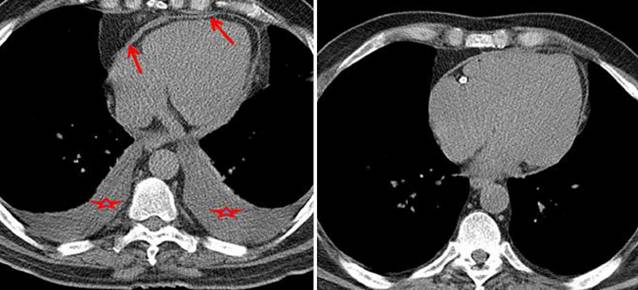

增厚的心包,胸水缩窄的症状

1个月激素治疗后,心包厚度正常

•CMR with intense delayed enhancement (red arrows) of the pericardium (left).

•After 6 weeks of prednisone therapy, the delayed enhancement was reduced (right).